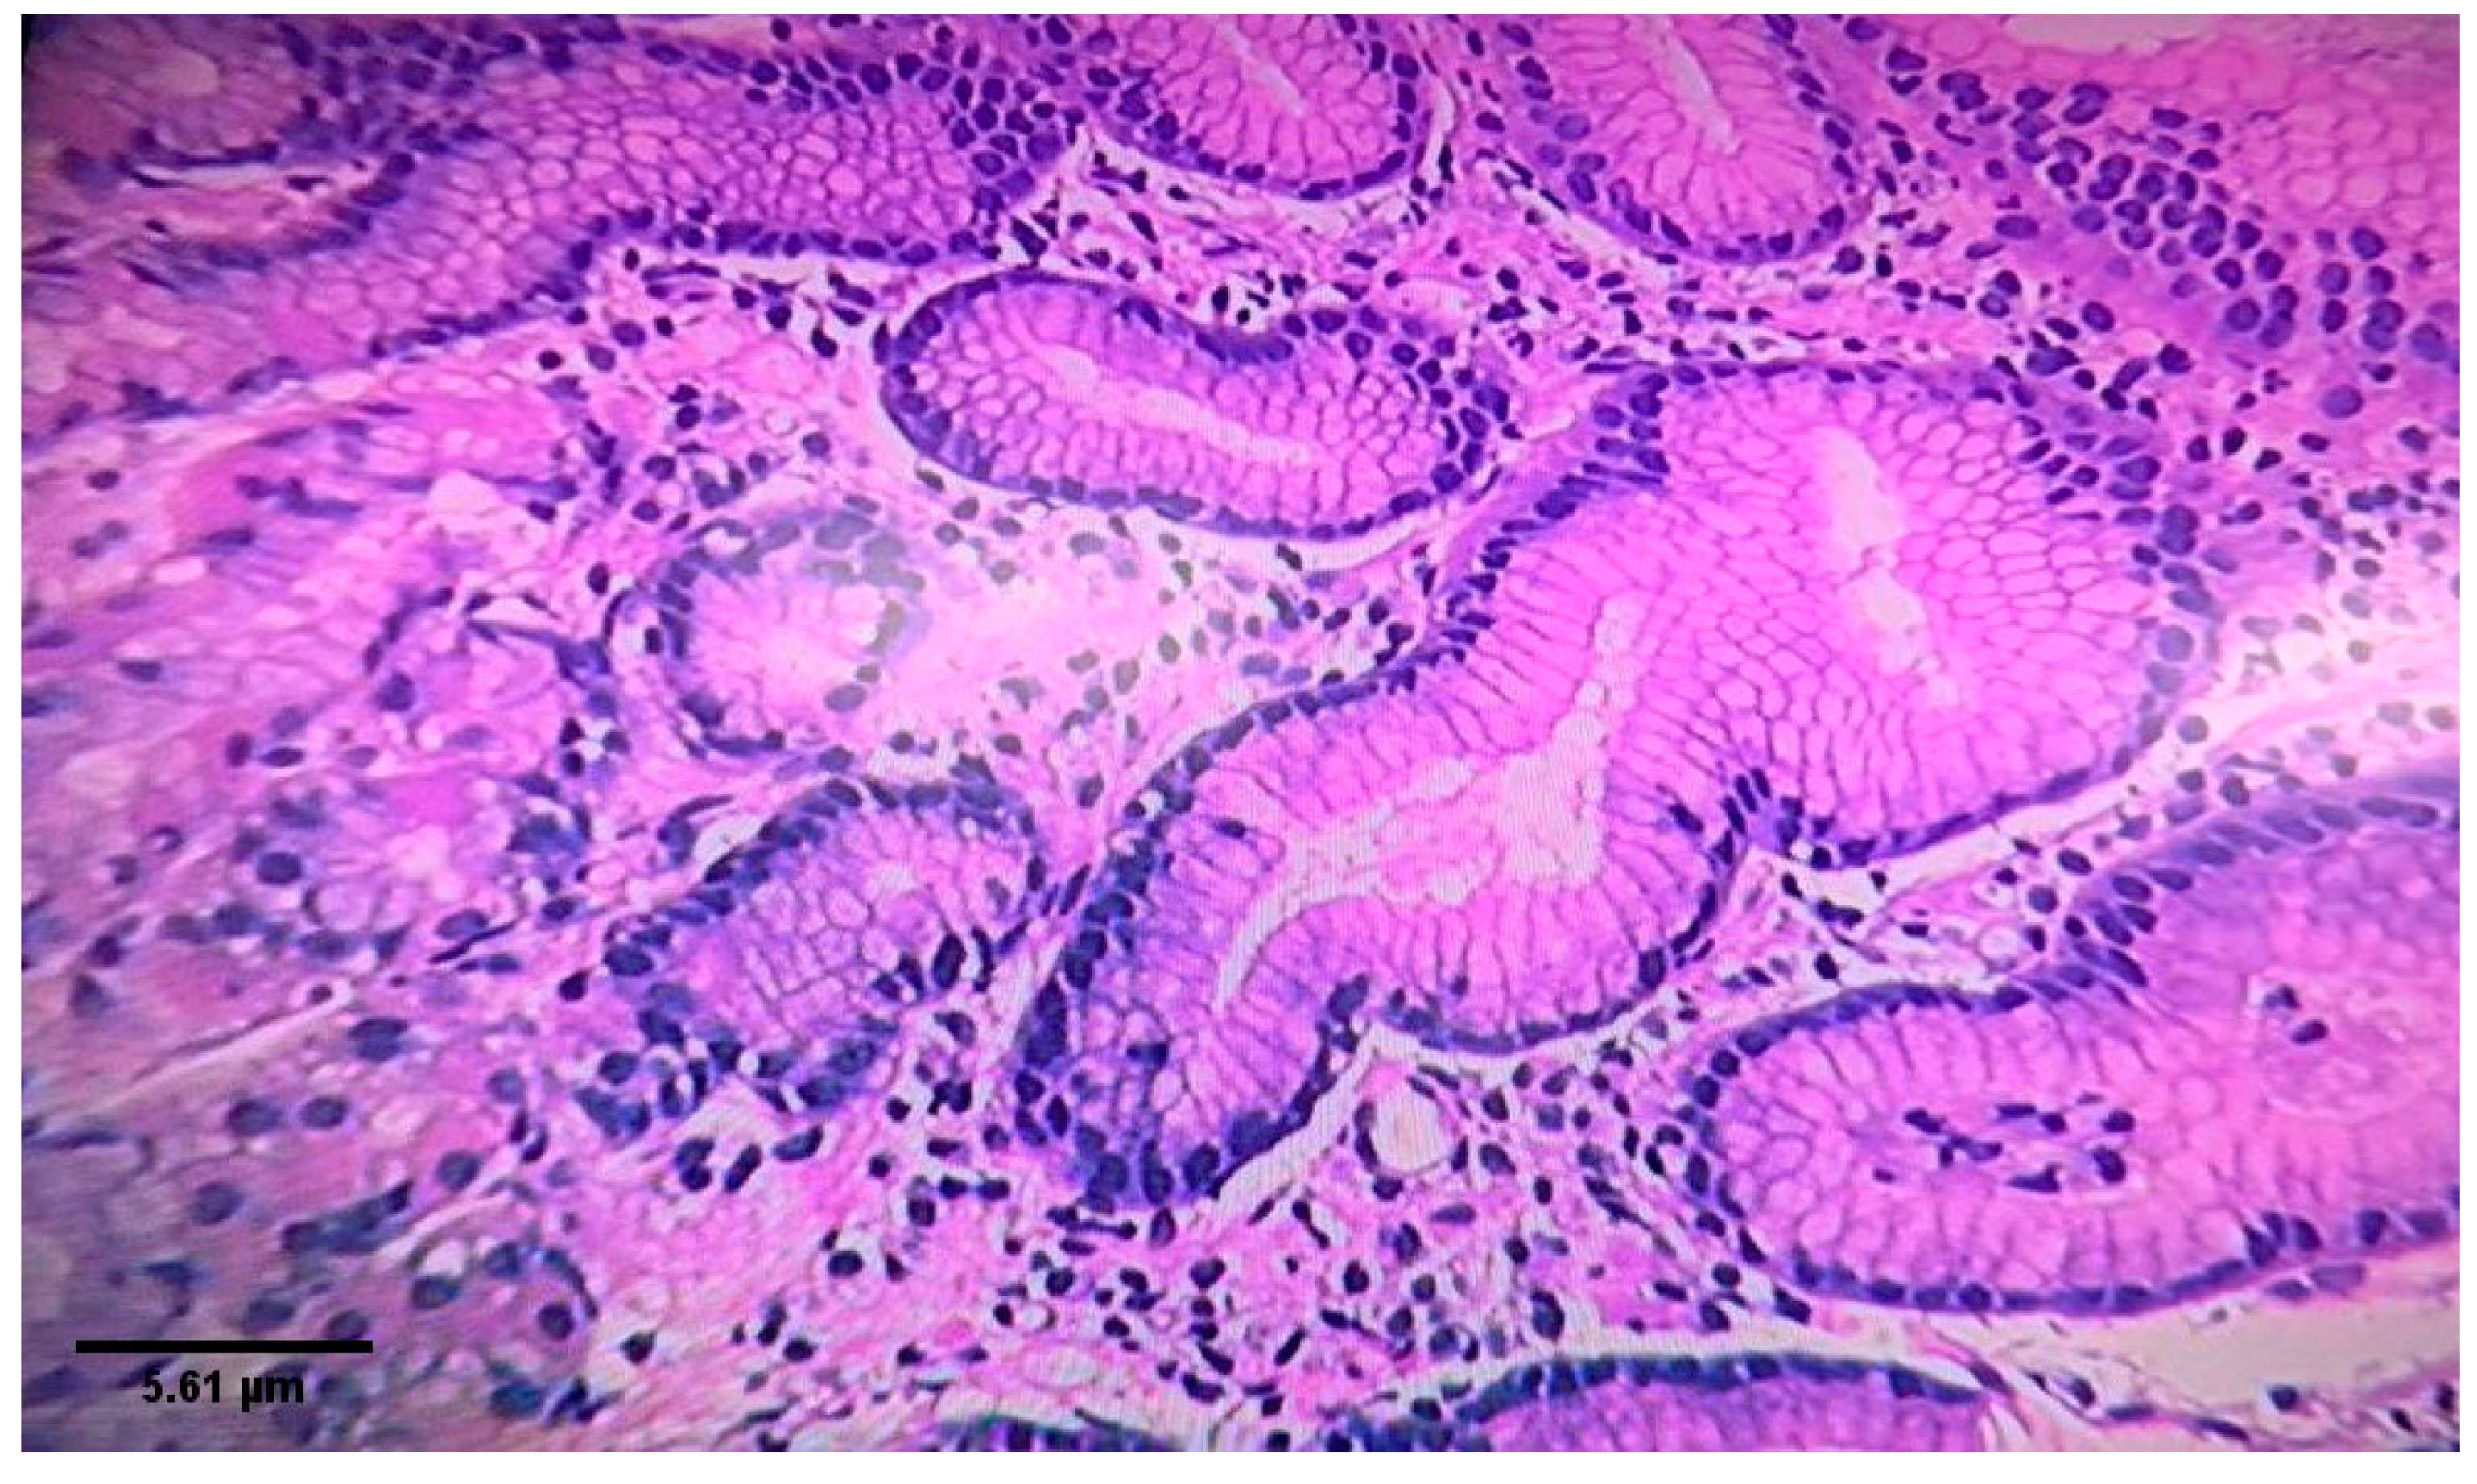

2.2. Endoscopy